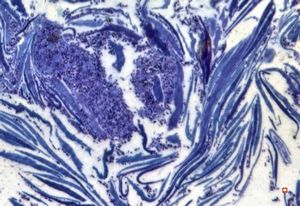

stabbed hypostom of the tick … toluidine-stained semithin section

stabbed hypostom of the tick … toluidine-stained semithin section (montage)